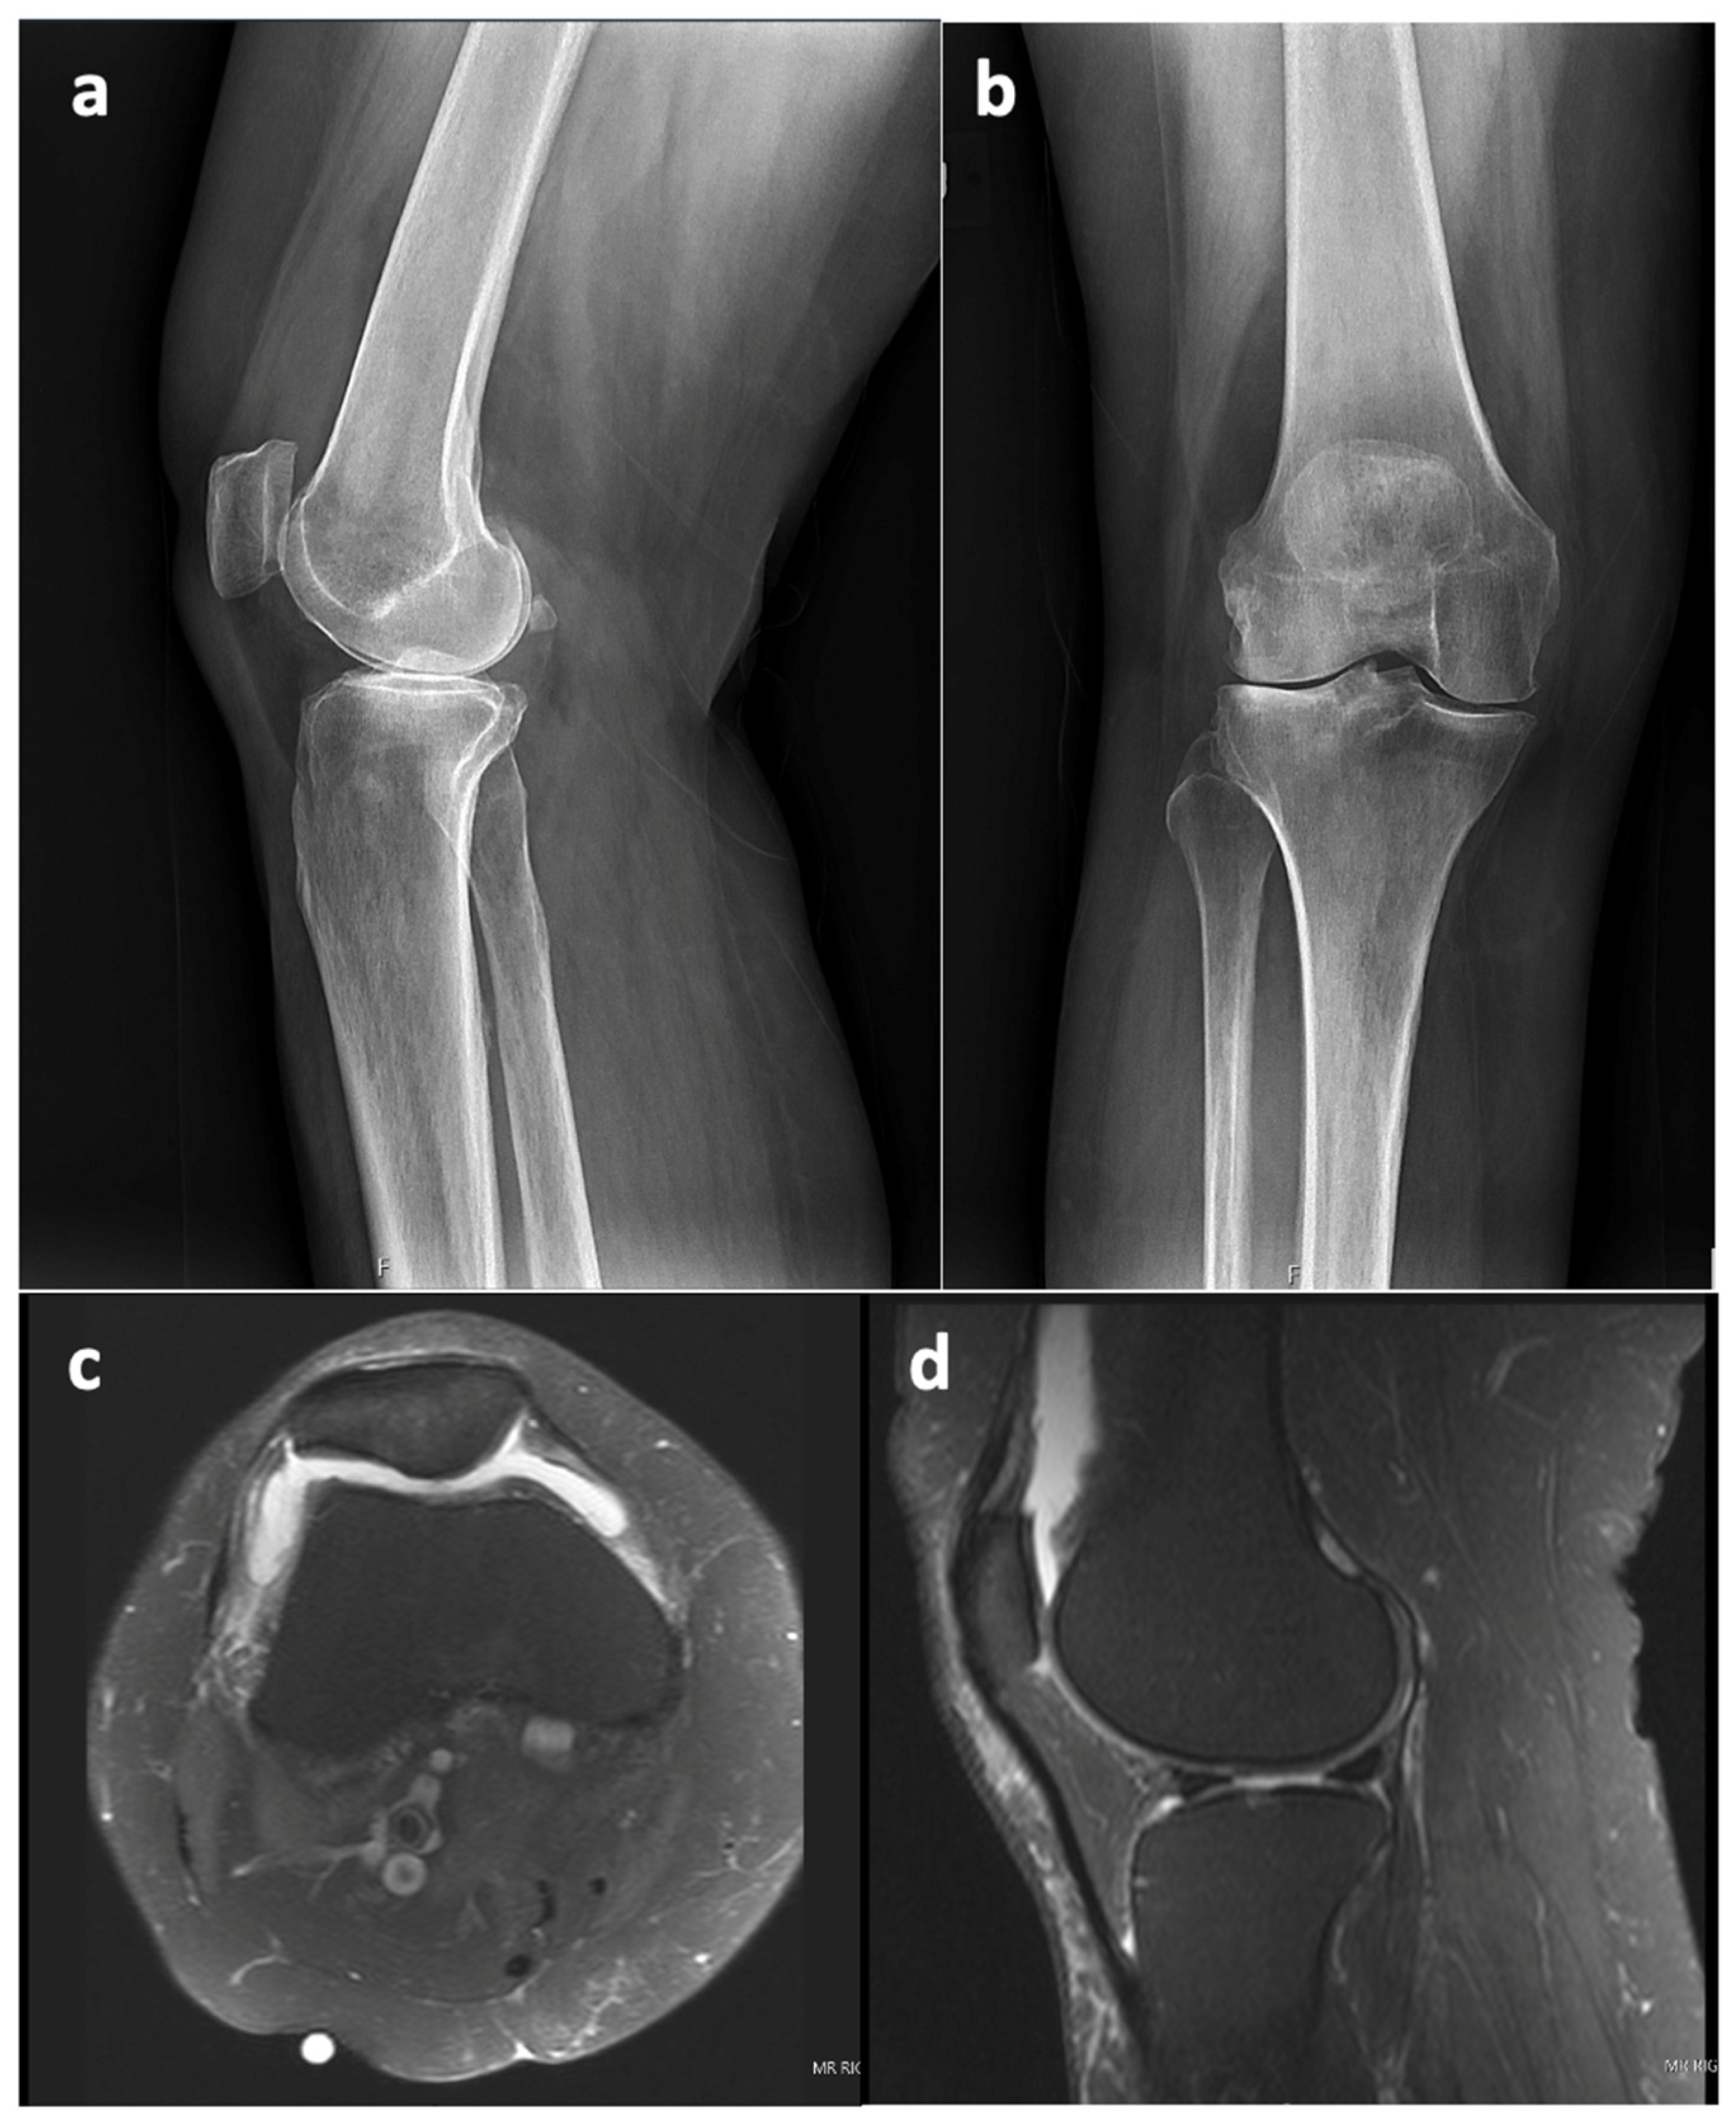

An MRI of the right knee was also performed and demonstrated pronounced debris-containing synovitis with the appearance of diffuse rice bodies in the anterior compartment and medial and lateral gutters (Figure 3). Distinguishing SC from rice bodies in the context of a PJI can be challenging. Rice bodies and SC both involve the formation of loose bodies, yet their origin and associated conditions vary. Additionally, the MRI appearances can be similar, making it hard to distinguish between the two. Both conditions can appear as multiple bodies within the joint space, with signal characteristics that can overlap. On the MRI, PJIs present as effusion and potentially synovial thickening, which might also complicate the distinction between rice bodies and synovial chondromatosis. In such complex scenarios, a histopathological examination is often necessary to confirm the diagnosis. The radiology report in this case stated that the presence of rice bodies (rice bodies are described as iso- and hypointense to skeletal muscle tissue, whereas SC would appear slightly hyperintense [10]) was compatible with the clinical concern of infection. However, the ability to rule out PJI was complicated by the patient’s elevated ESR and CRP and the diagnosis of anti-phospholipid syndrome with positive rhetological markers (ANA+).

Figure 3. MRI of right knee 3 October 2022 (GE, Coil: HD TRknee PA): (a)—sagittal plane (proton density—PD), (b)—axial plane (PD). Dotted red line outlines the appearance of diffuse rice bodies in the anterior compartment and medial and lateral gutters.